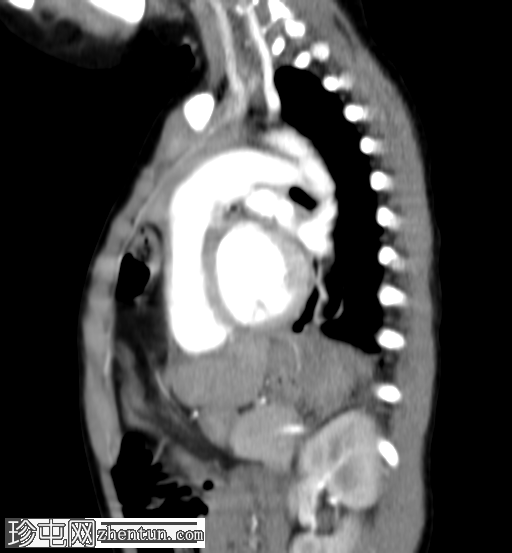

4.png

轴位增强扫描

动脉期

5.png

矢状位增强扫描

横结肠及其系膜经膈前部缺损疝入前纵隔。

未见肠管扩张或梗阻。

双肺实变影,提示呼吸道感染。